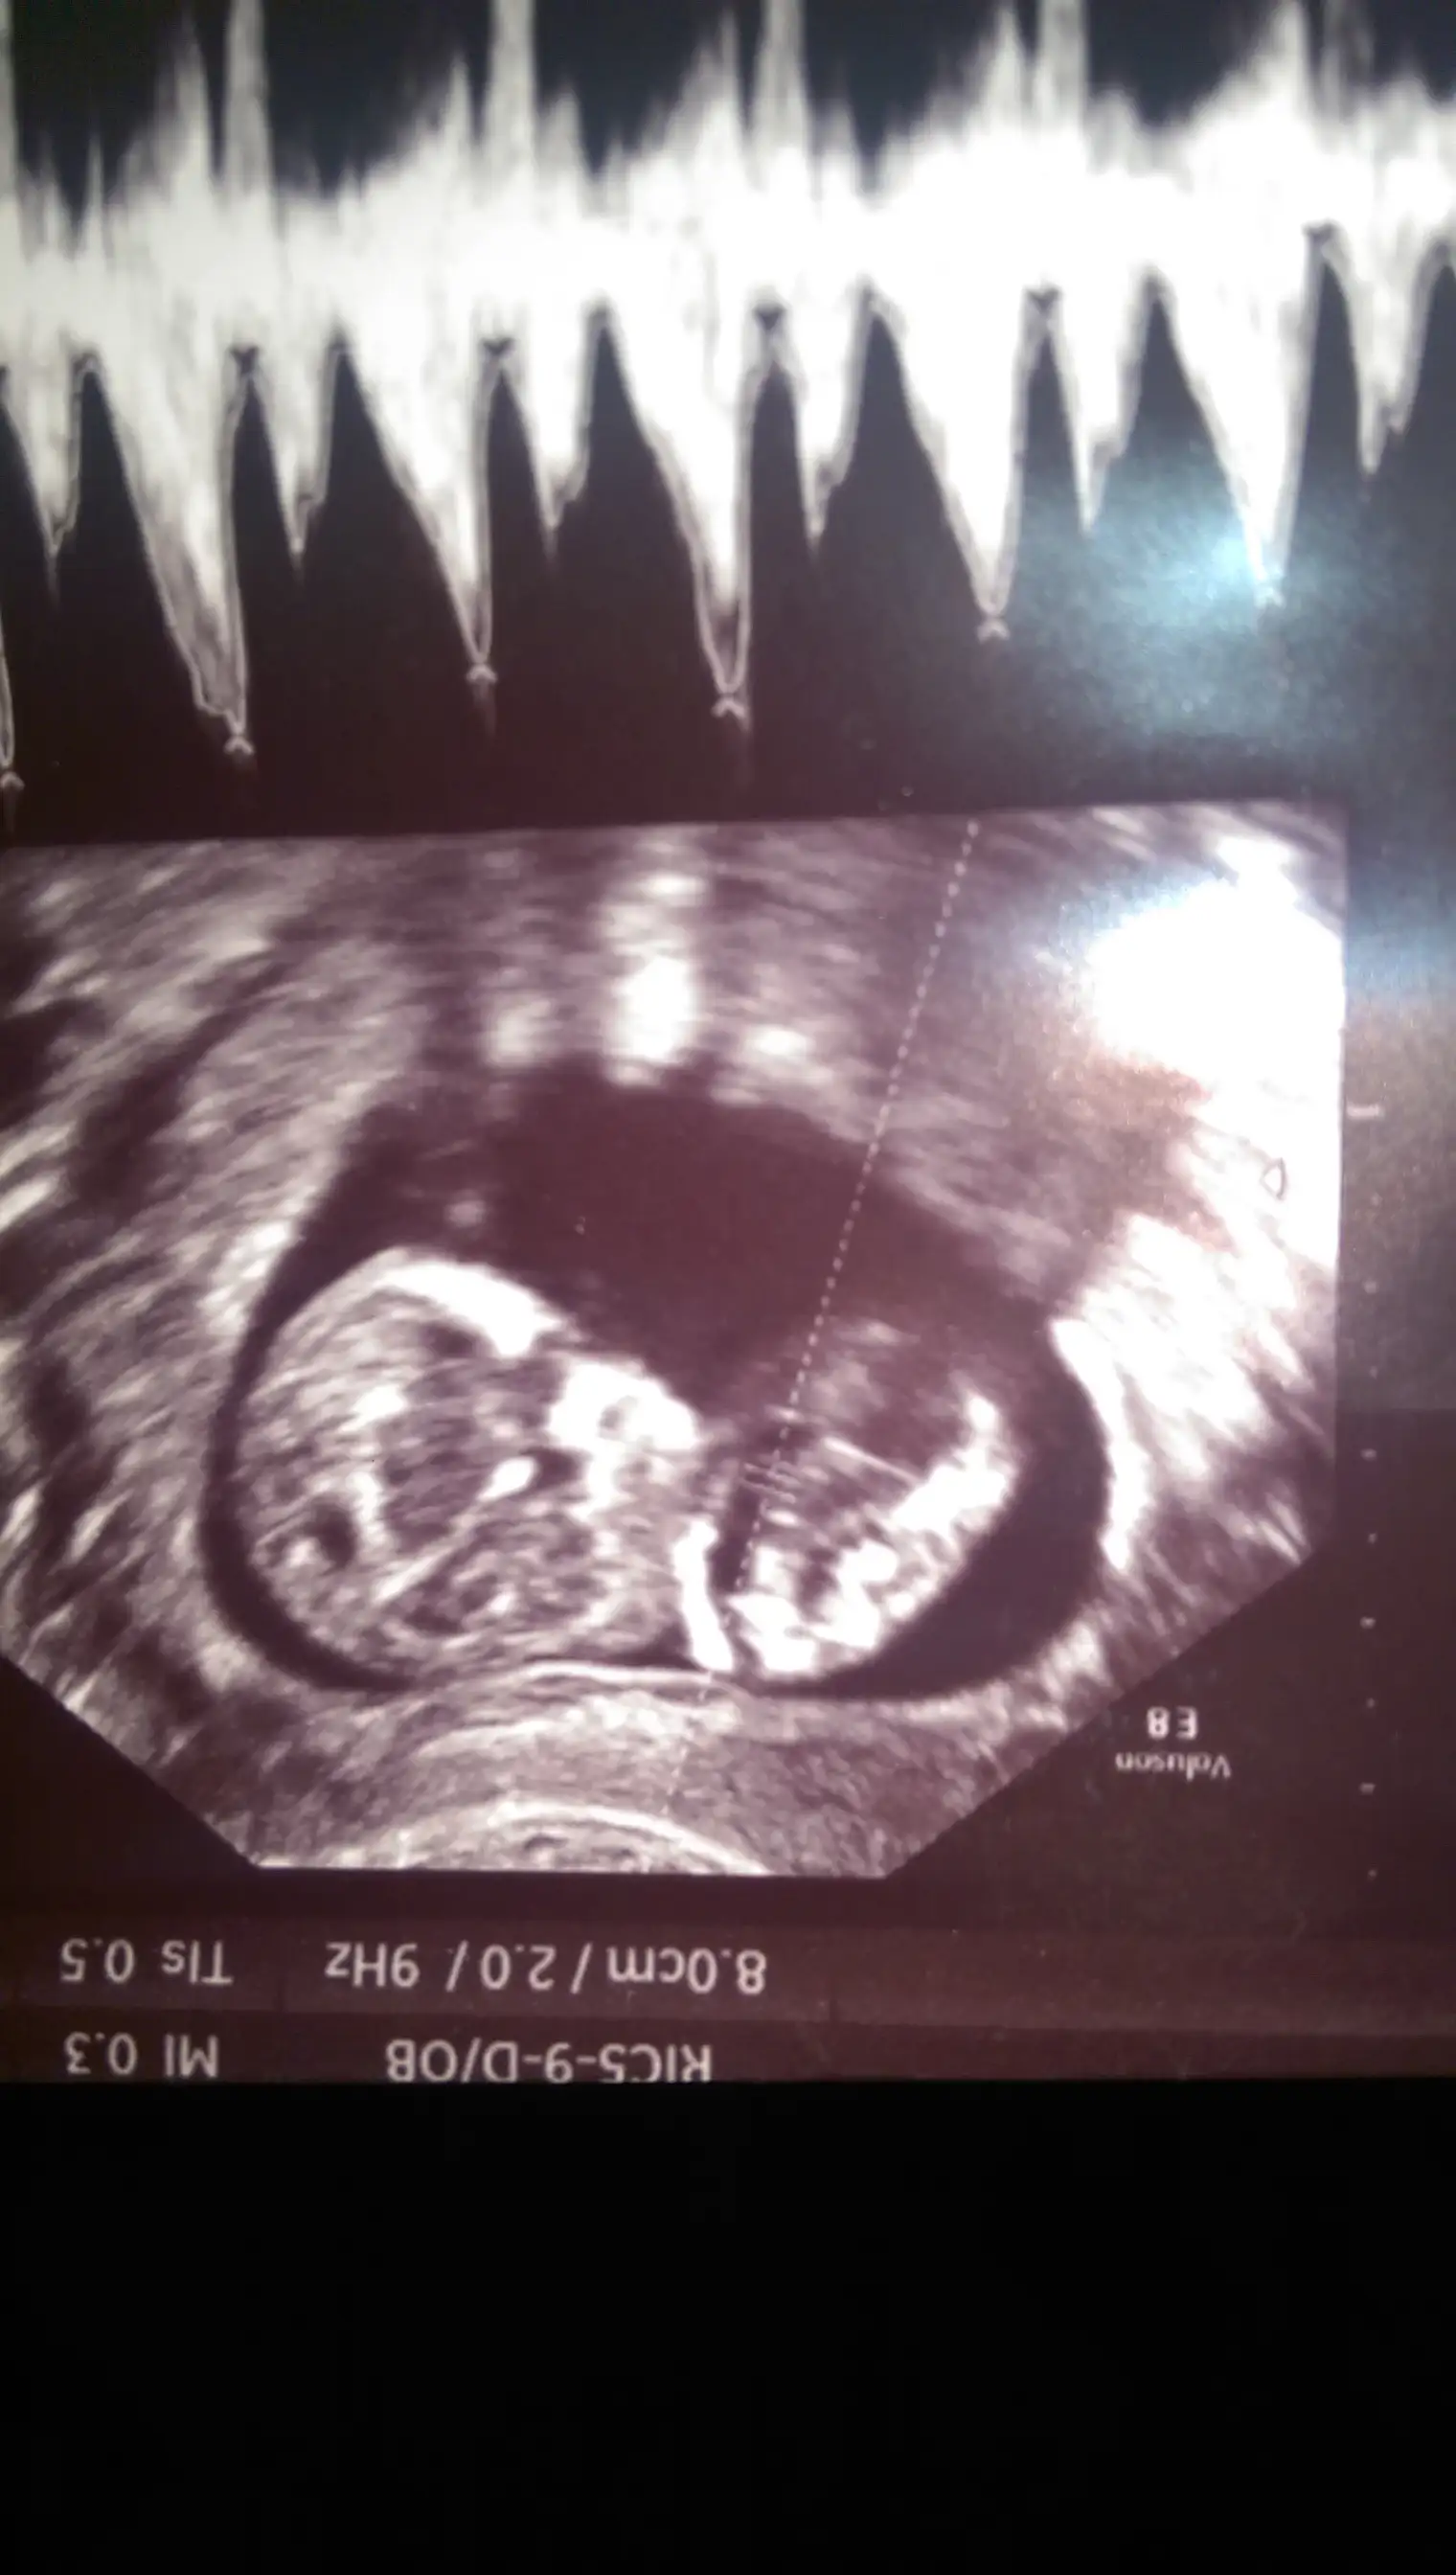

dr soylemeden siz gorun genital nub teorisi ( bebegin cinsiyeti)

Ustteki fotoda erkek gibi eger kordon degilse digerlerinde kiz gibi doktor bisey dedimi

Canim esim bebisi videoya cekmisti ordan kopyaladigim bir resmi ekledim doktorun tam cikintisini isaretleyip gosterdigi yerin resmi. Onuda paylasmak istedim bi bakarsin tekrar doktorla ayni fikirdemisiniz merak ettim senin yorumunuda :anneadayı: